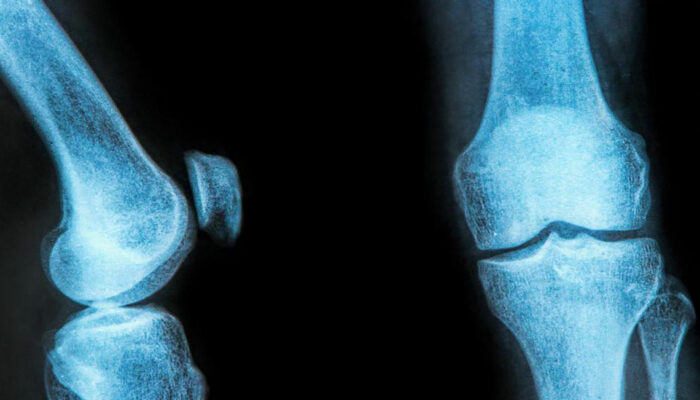

The rubbery C-shaped disc cushioning your knee is a meniscus. There are two menisci in each knee. One at the inner side and the other on the outer side. It is this meniscus that helps to keep your knee steady. It balances your body weight around your knee. If there is a tear in the meniscus, you will experience a lot of pain. It will also prevent the proper functioning of your knee.

A meniscus tear happens when the knee is twisted or turned abruptly while the foot is still flat on the ground. It can occur due to heavy weight lifting or while playing high-impact sports. A brace for meniscus tear can prevent and protect you from further injury.

You can distinguish the types of meniscus tear based on its symptoms. The types can range from being minor to more severe tear. A minor tear involves a slight swelling of the knee and can last up to 2 to 3 weeks. If the swelling has aggravated after a sudden twist or turn, you might be experiencing a partial tear. In this regard, a moderate medial or lateral meniscus tear brace can ease the pain.

In the case of a moderate tear, the pain lies in the center of the knee. The swelling is visible over 1 or 2 days. In this case, walking is possible, but the bending of the knee might cause stiffness. The symptoms arrive and withdraw over a prolonged period. They can cause enough trouble unless treated at the right time. A meniscus tear brace with two sturdy aluminum uprights and bilateral hinges will be beneficial in the case of a moderate tear.

A severe tear is considered as an extreme case. A severe tear tends to happen when the meniscus flows into the knee joint area. You will find it difficult to walk, bend, or turn your knee. You might feel that your knee seems locked up. Sometimes, the swelling returns after 2 to 3 days of the injury. So, often you might not even realize that you suffer from a meniscus tear. A thigh and calf strap will help to compress the knee joint, effectively relieving the pain.